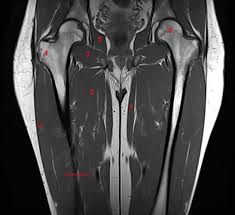

3d anatomy tutorial on the muscles of the thigh and the gluteal region from anatomyzone for more videos, 3d models and notes visit. Like the forearm, the upper leg, or thigh, has a dense arrangement of many muscles. It's the area that runs from the hip to the knee in each leg. The femoral artery gives off the deep femoral artery or profunda femoris artery and descends along the anteromedial part of the thigh in the femoral triangle.it enters and passes through the adductor canal, and becomes the popliteal artery as it passes through the adductor hiatus in the. Medial muscles adduct and rotate your thigh, and posterior flex your leg and extend your thigh. All the medial thigh muscles are innervated by the obturator nerve, which arises from the lumbar plexus. The femoral artery is a large artery in the thigh and the main arterial supply to the thigh and leg. Each compartment has a distinct innervation and function.

There are five muscles in this group; People who play soccer have these specific muscles of the leg very well defined, so they're like a walking anatomy atlas for thigh muscles. Upper_thigh_muscle_anatomy 2/3 upper thigh muscle anatomy doc upper thigh muscle anatomy upper thigh muscle anatomy muscle anatomy reference charts author: Posterior compartment, also known as the flexor compartment; The femoral artery gives off the deep femoral artery or profunda femoris artery and descends along the anteromedial part of the thigh in the femoral triangle.it enters and passes through the adductor canal, and becomes the popliteal artery as it passes through the adductor hiatus in the. The following diagram illustrates the actions of the terms adduction, abduction, flexion and extension at the different joints. Medial muscles adduct and rotate your thigh, and posterior flex your leg and extend your thigh. The femoral artery is a large artery in the thigh and the main arterial supply to the thigh and leg. Anterior compartment, also known as the extensor compartment; The anatomy of inner thigh muscles. Upper leg anatomy and function the upper leg is often called the thigh. The adductor group, commonly known as the inner (upper) thighs, is a group of several muscles that, when engaged, move the legs together upper thigh anatomy. The thigh has three sets of strong muscles:

The thigh bears much of the load of the body's weight when a person is upright. 3d anatomy tutorial on the muscles of the thigh and the gluteal region from anatomyzone for more videos, 3d models and notes visit: •medial thigh muscles•adductor longus muscle•adductor magnus muscle•adductor. It's the area that runs from the hip to the knee in each leg. The musculature of the thigh can be split into three sections;

•medial thigh muscles•adductor longus muscle•adductor magnus muscle•adductor. Each compartment has a distinct innervation and function. (musculus iliopsoas) iliopsoas is a large compound muscle of the inner. But in all reality, even a stepping motion or holding one position for too long can result in an inner thigh injury. The inner thigh muscles anatomy shows that there are 5 different types of muscles in inner thighs area which are called pectineus, gracilis, adductor brevis, adductor longus and adductor magnus and the combination of these five major muscles group is called adductor. The rectus femoris is located in the center of the thigh, while the vastus medialis is in the middle of the said body part. The thigh is the area between the hip and the knee joint. An inner thigh strain is common among athletes and those who sometimes use sporadic twisting movements in their exercises. May 31, 2021 reading time: Upper_thigh_muscle_anatomy 2/3 upper thigh muscle anatomy doc upper thigh muscle anatomy upper thigh muscle anatomy muscle anatomy reference charts author: The muscles in the medial compartment of the thigh are collectively known as the hip adductors. Pelvic & upper thigh anatomy. The adductor brevis, adductor longus and adductor magnus make up the the starting position is lying on the right side where the upper body is supported by the right arm.